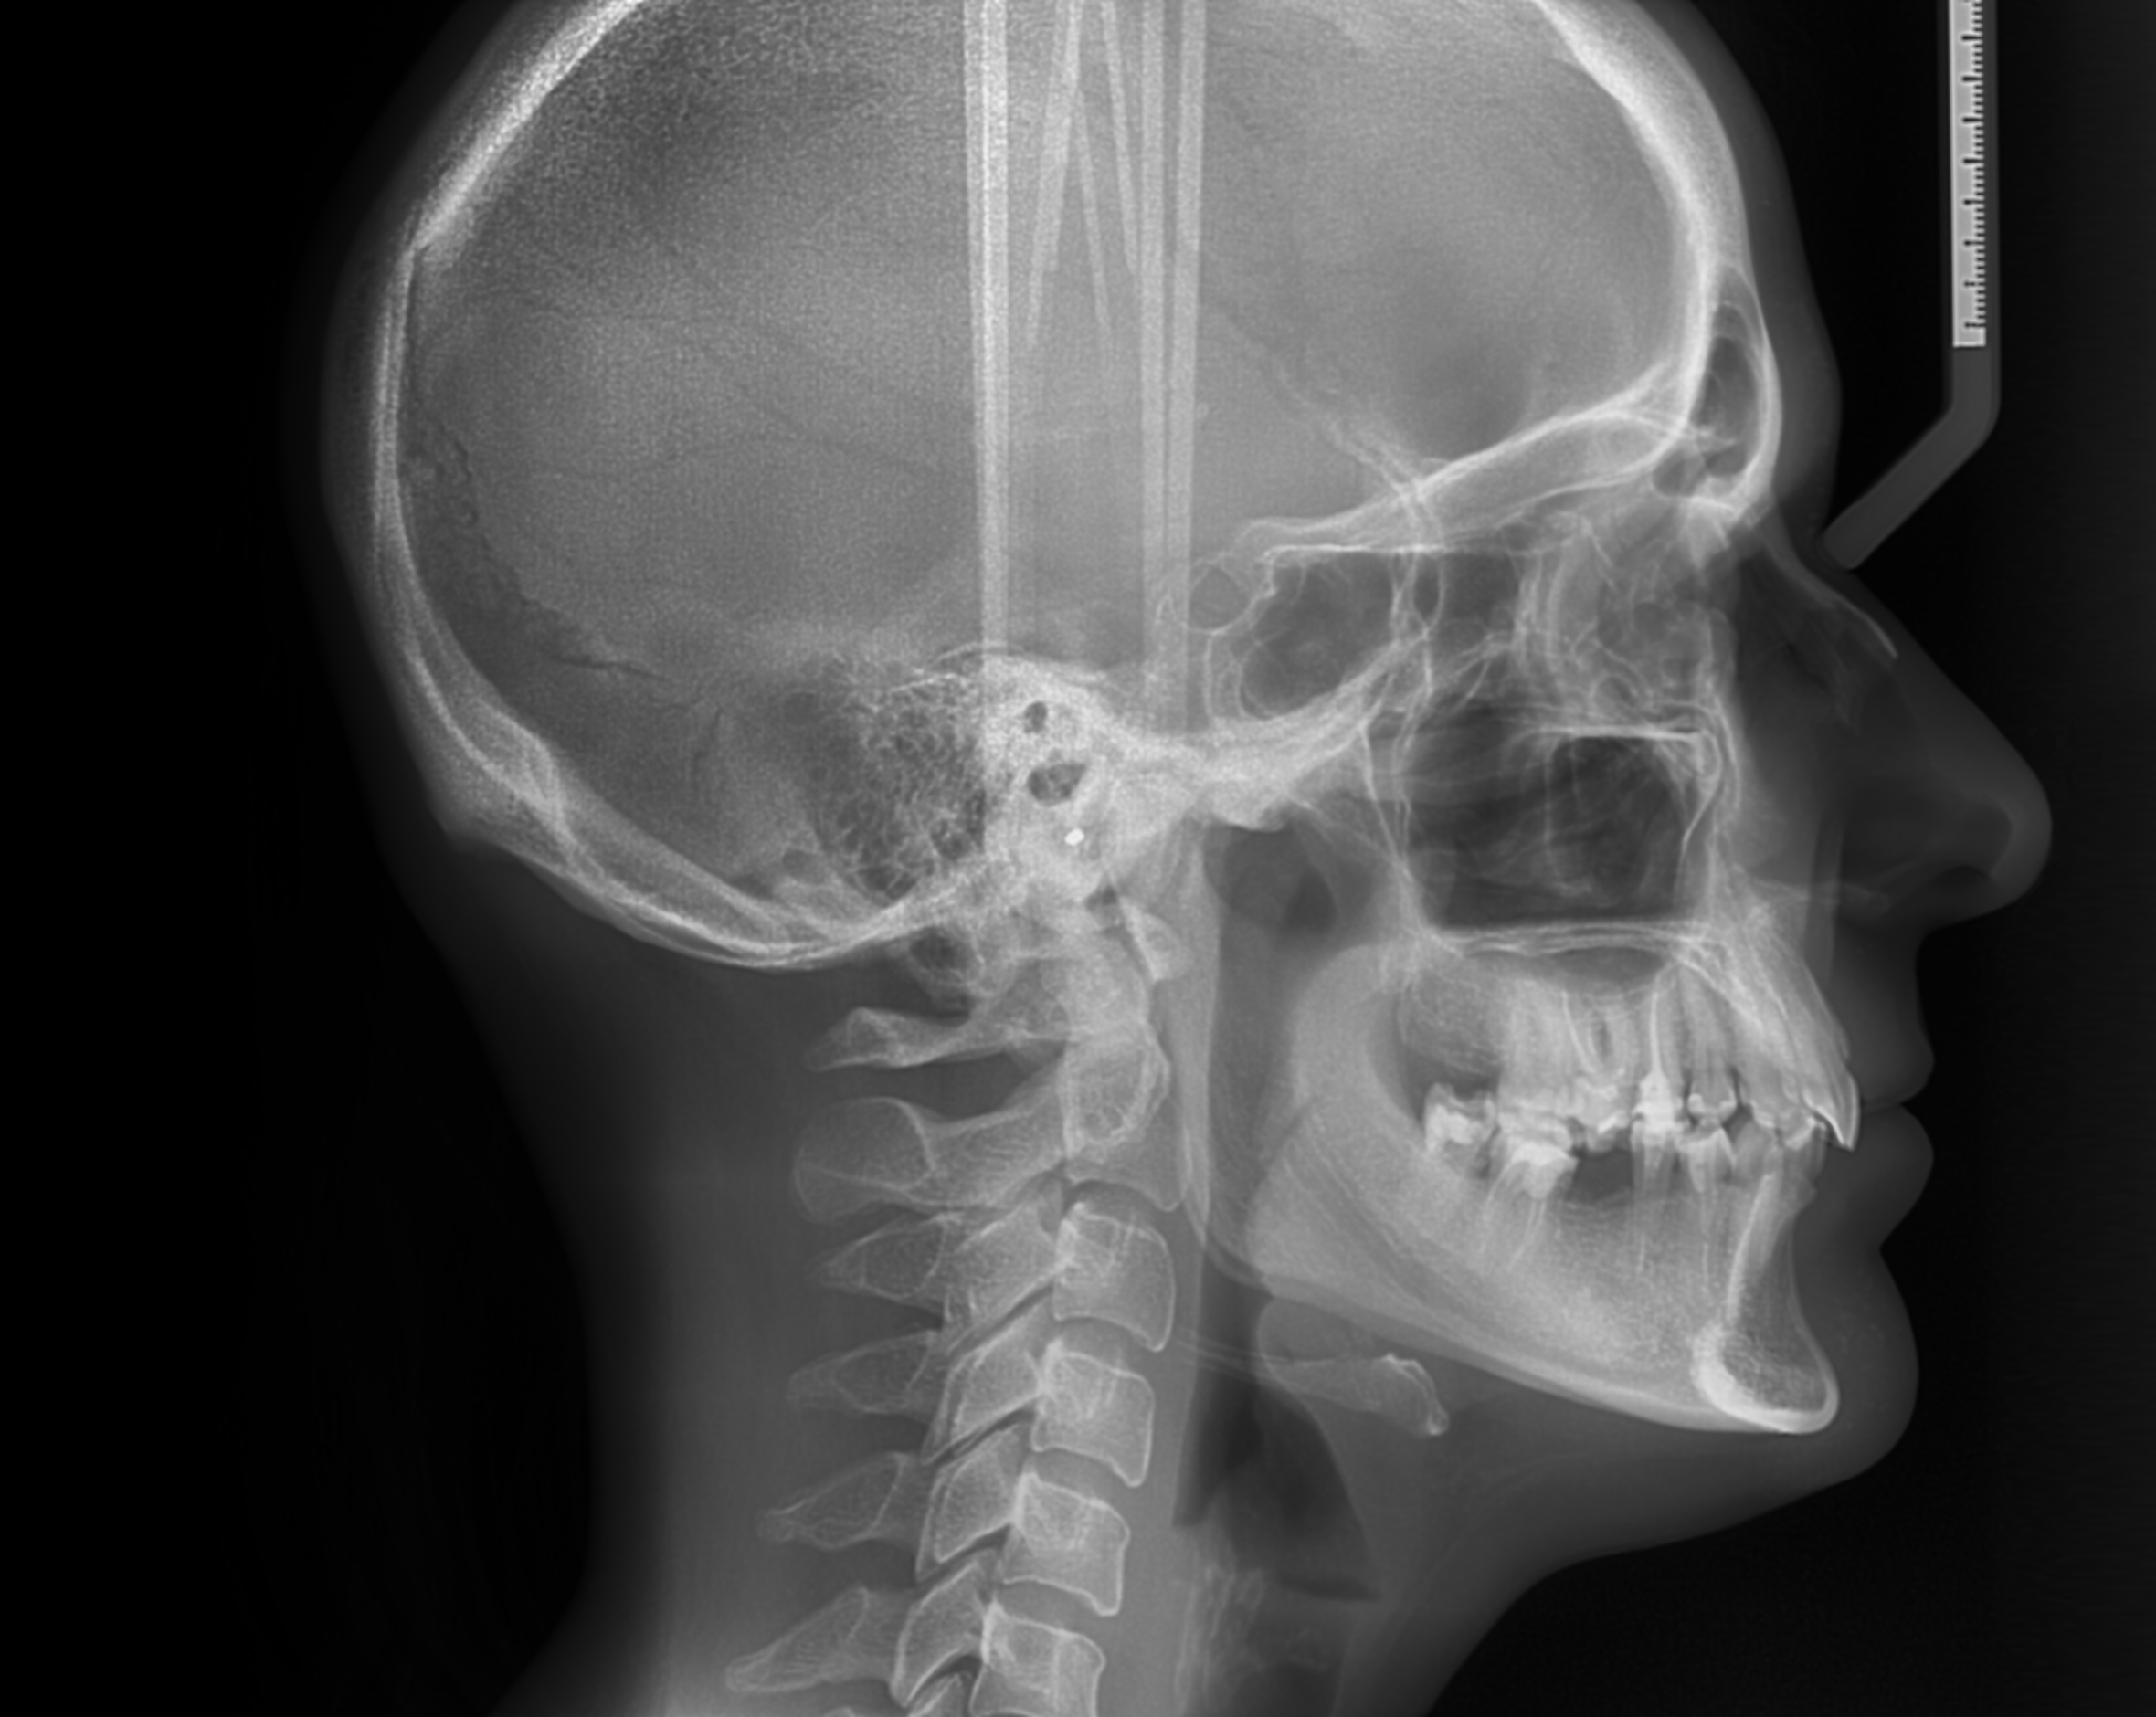

Telerentgen

Stranski telerentgenogram ali cepfalostat glave je del morfološke diagnostike v čeljustni in zobni ortopediji.